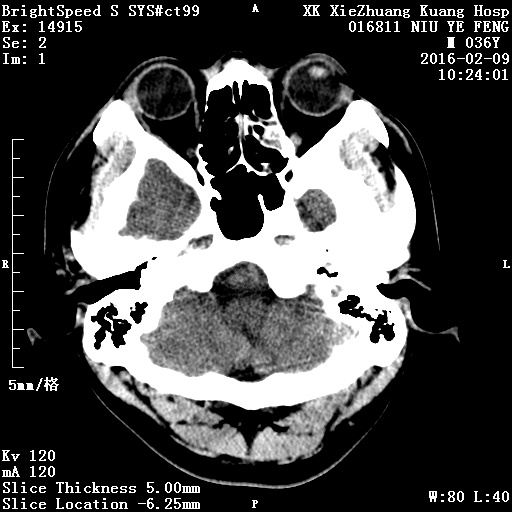

CT51599:颅脑

本帖最后由 cefcmj 于 2016-2-10 19:48 编辑 同行们,过年好。昨日凌晨2点突发头痛,意识清楚,肢体无障碍,自行骑车前来就诊。有肿瘤性出血可能吗?

右侧枕叶血肿,年轻人多为血管畸形所致,建议MRI检查。

右侧枕叶可见团块状、斑点状高密度影,无明显水肿及占位效应,考虑:右侧枕叶血肿(血管畸形所致)。

1、右侧枕叶血肿,周围轻度水肿,考虑蛛网膜下出血可能,建议进一步检查。血管畸形?2、左侧筛窦炎症。

右侧枕叶血肿(不排除脑血管畸形所致可能)。

建议:行CTA或DSA检查。